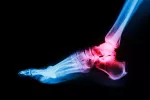

- A continuación se produce la formación de cristales en las articulaciones, que dará lugar al síntoma más característico de la gota, conocido como ataque agudo de gota. Como su nombre indica, este ataque tiende a presentarse de forma repentina, afectando a una o varias articulaciones. El enfermo sufre un dolor muy intenso, que normalmente comienza durante la noche, y que cede al cabo de los días o las semanas. Externamente, la piel aparece caliente y enrojecida y es extremadamente sensible al tacto (puede llegar a resultar molesto el roce de la sabana o cualquier otro contacto físico). Como síntoma secundario, en ocasiones puede aparecer fiebre.

- La tercera fase sería la cronificación de la enfermedad, denominada artritis gotosa. Esto ocurre cuando se da la repetición de los ataques, lo cual puede suceder mucho tiempo después del primero de estos. La reaparición de los síntomas de la gota suele ser más prolongada en el tiempo, y normalmente afecta a un mayor número de articulaciones que el ataque agudo. Una vez superado el ataque, los síntomas desaparecen por completo, al menos al inicio de la enfermedad, ya que a medida que esta se cronifica y los ataques comienzan a repetirse, el tiempo que transcurre entre un episodio y el siguiente va disminuyendo y quedan molestias en la zona afectada.